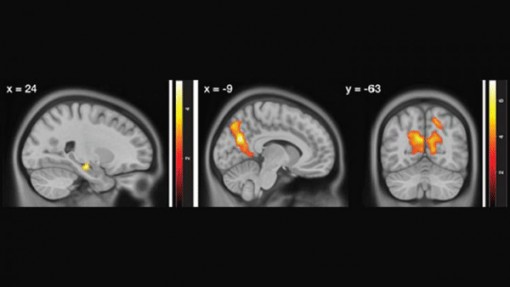

Hoạt động não quá mức có thể gây bệnh Alzheimer

Bên cạnh nỗ lực tìm ra phương pháp chữa trị, các nhà khoa học vẫn luôn cố gắng tìm hiểu nguyên nhân khiến một số người phát triển bệnh Alzheimer còn những người khác thì không.